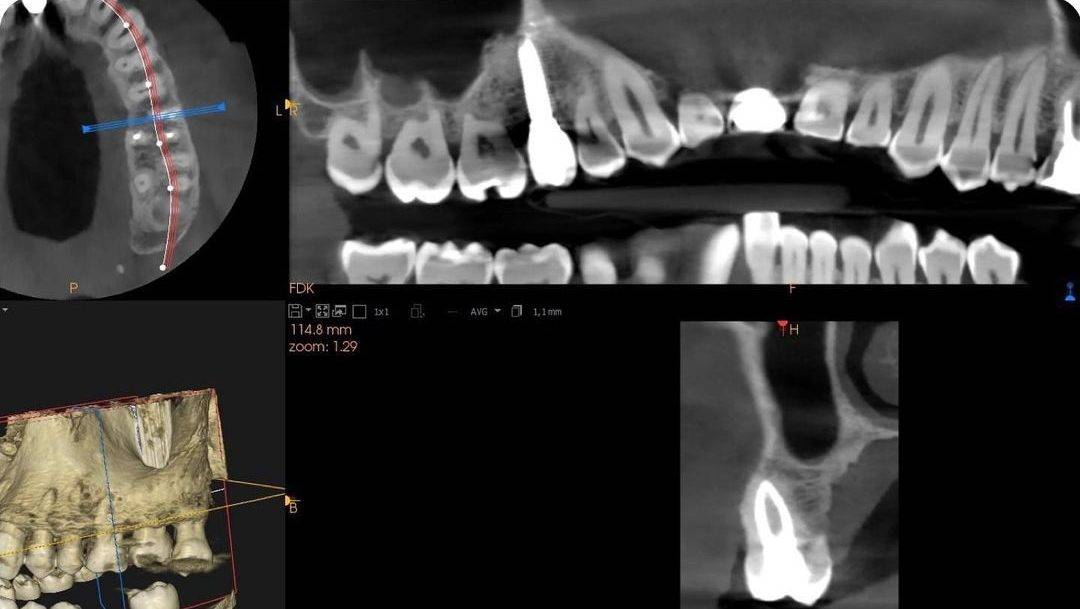

Tratadores de conducto endodoncia en 26 e implante dental en 15. Revisión a los 18 meses.